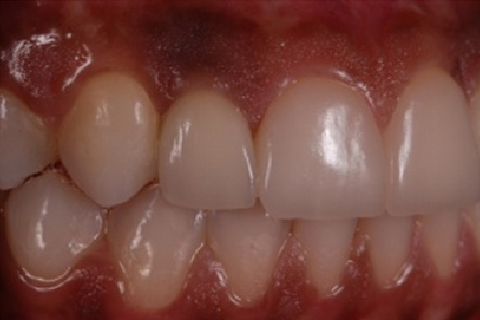

''Neste caso, a paciente gostaria de melhorar a estética do seu sorriso, prejudicada pela agenesia de ambos os incisivos laterais superiores. Devido à baixa disponibilidade óssea, observada na tomografia computadorizada, optou-se pela instalação de implantes estreitos (Xive – Dentsply Implants – 3.0 mm de diâmetro) com regeneração simultânea (Biooss e Biogide – Geistlich), ao invés de realizar enxerto ósseo prévio. Após osseointegração, foi realizado condicionamento gengival com provisórios e novo enceramento diagnóstico. O caso foi finalizado com coroas livres de metal sobre os implantes e microlaminados cerâmicos sobre os incisivos centrais (e.max - dissilicato de lítio – Ivoclar Vivadent), visando o mínimo desgaste de estrutura dental sadia. ''